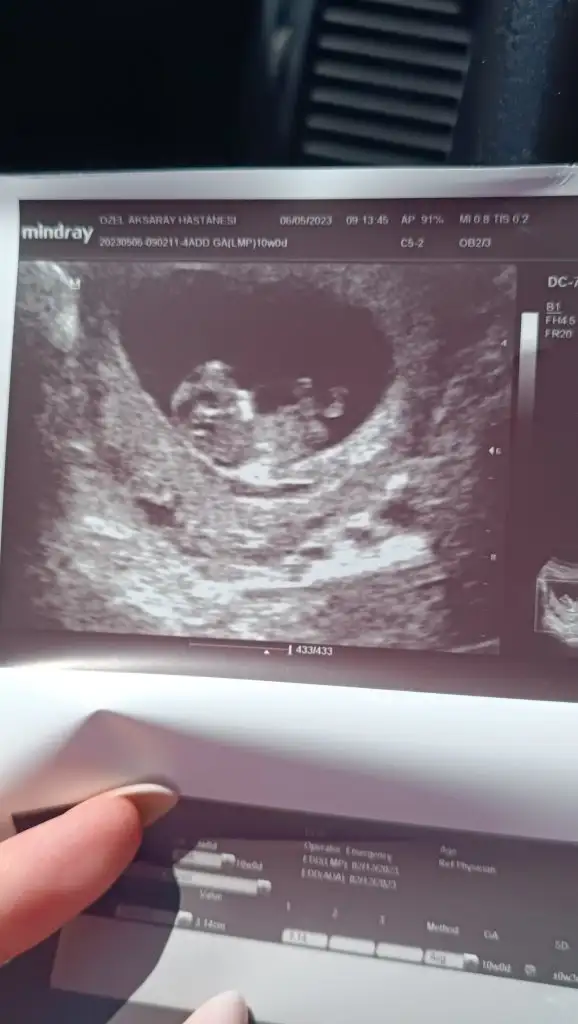

Bugün tam 10 haftalık karından plasentayı da çizdim doktor söyledi orası olduğunu tahminini bekliyorumBurada kaç haftalık? Parlak alan solda gibi eğer karından ultrason ise erkek diye anlıyorum :)

10 haftalık karından bi tahmin alabilir miyiz lütfeeeeenMaşallahsanırım 9 haftalık bana kız gibi geldi ama tamamen öylesine his